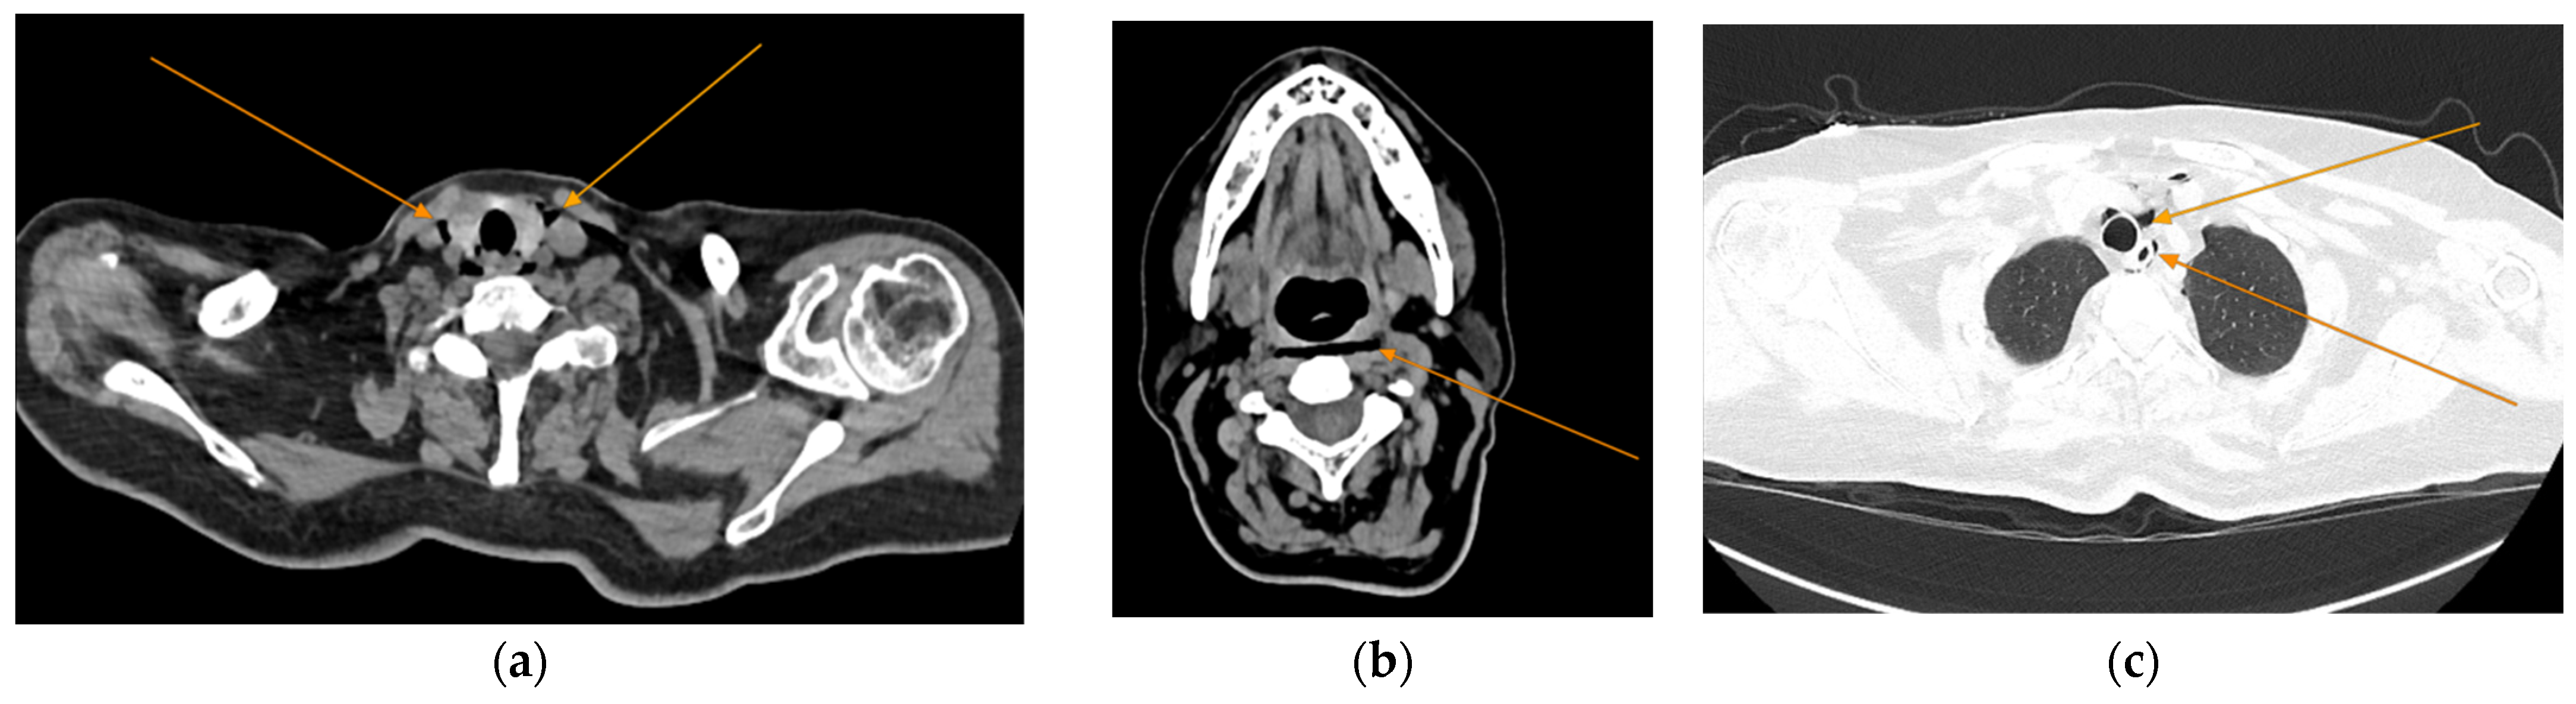

Given the patient’s history of vomiting, and consulting with the thoracic surgeon, a second CT scan with oral contrast was performed approximately 3 h later, after initial stabilization of the patient, to rule out an esophageal rupture. The subsequent imaging revealed the progression of the pneumomediastinum, with increased extension into the cervical region, including the peritracheoesophageal, perithyroidal and retropharyngeal spaces (Figure 3), without evidence of esophageal rupture (Figure 4). Oxygen therapy and empiric antibiotic therapy were initiated in the ED as initial treatments of this condition.

Figure 3.

Repeated chest and neck CT scans showcasing extension of the pneumomediastinum (arrows), axial views: (a) air tracking into the cervical soft tissues and prevertebral space; (b) air around airway structures; (c) pneumomediastinum surrounding the trachea.